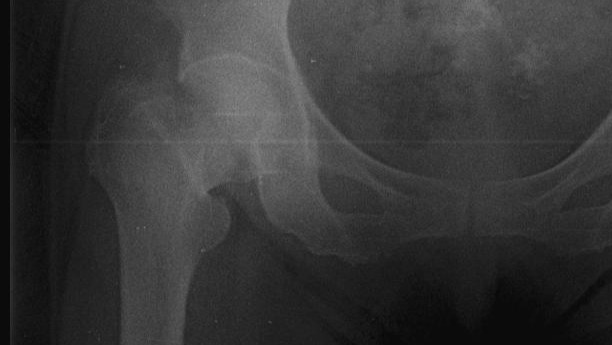

English: A few days ago, my grandmother suffered a fall that fractured her hip bone which connects to the femur. She is in a grave state and cannot stand or walk at all. Before this she had already suffered from cataracts in her eyes, leaving her vision at no more than 30%. Not being able to walk or be mobile has severely affected her mental state because now she can't move or see well.

The only option to heal her hip is an immediate surgery wherein a prosthetic hip would replace her broken one allowing her to walk in less than a week. Safe, reliable medical centers in Venezuela are few and far between so finding one that is willing to do this surgery is extremely expensive and not covered by any sort of insurance.

I'm attaching pictures of the fracture as well as the prosthetic surgery that would completely restore her hip.